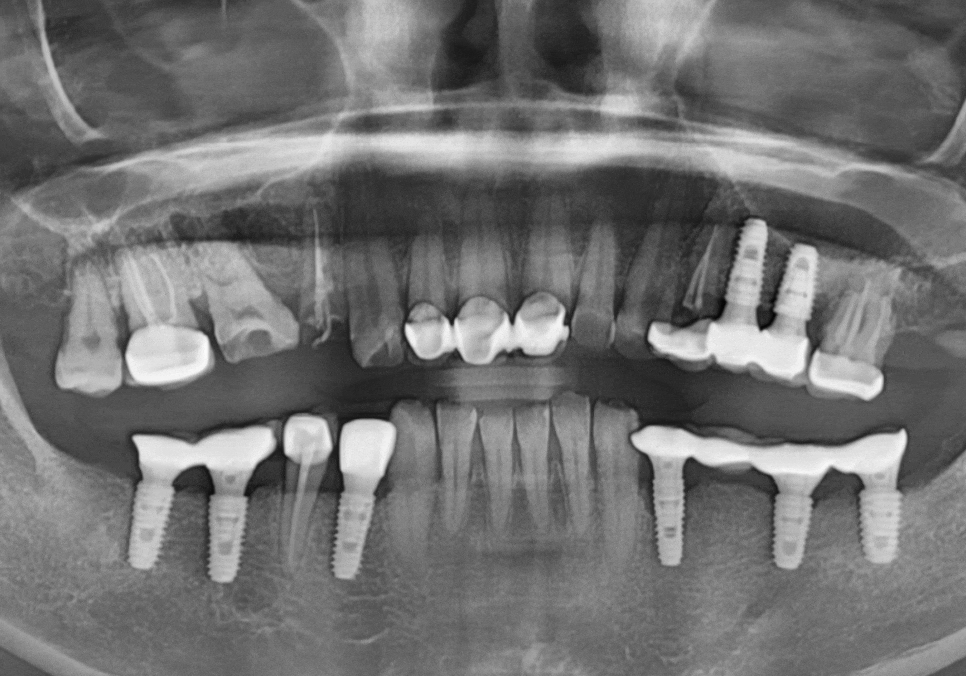

보철이 빠져서 내원한 환자분 사례

강동구 오래된 보철, 교체 시기는? 아프지 않은데 꼭 바꿔야 하나요?

최근 저희 치과를 찾으신

한 환자분의 사례입니다.

오른쪽 위 어금니에 씌운

10년 된 보철물이 갑자기

툭 빠져서 내원하시게 되었는데요~

251223

겉보기엔 멀쩡해 보였지만

보철물이 빠진 자리의

내부 치아 2개는 이미 까맣게

썩어있는 상태였습니다.

결국 뿌리 끝까지 염증이 퍼져

치아가 흔들리고 있었기에,

안타깝게도 이 치아는 살리기가 어려워

발치 후 뼈이식을 동반한 임플란트를

진행하게 되었습니다.

260102

다행히 오른쪽 앞니(#11)는

뿌리 끝 염증이 진행 중이었지만,

흔들림도 없고 치질의 양이 꽤 남아있어서

신경치료를 통해 치아를 살려보기로 했어요.

260109